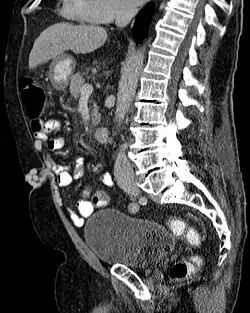

Ein Caput Medusae (lateinisch für Kopf der Medusa) ist ein klinisches Zeichen, das sich in Form von sichtbarer Ausdehnung geschlängelter Venen (Venae paraumbilicales) im Bereich des Bauchnabels infolge einer Blutstauung durch eine portale Hypertension zeigt.

Durch eine pathologisch bedingte Stauung im Pfortaderkreislauf der Leber (meistens durch Leberzirrhose) kommt es zur Vergrößerung der portokavalen Anastomosen, die das Blut in einem Umgehungskreislauf der unteren Hohlvene (Vena cava inferior) und somit dem Herzen zuführen. Die unter der Bauchdecke im Bereich des Bauchnabels gelegenen Venae paraumbilicales werden durch die erhöhte Belastung ausgedehnt und unter der Haut sichtbar.